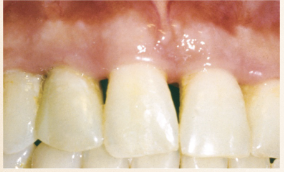

Describe the tissue contour in this image?

Blunted papilla